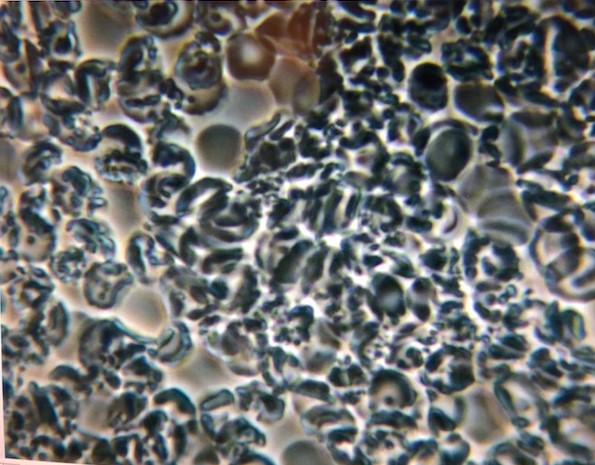

I arrived t the clinic and was handed the schedule for the ten days. First thing I noticed was that there is no scheduled three meals for the day! Oh my God! I am not going to eat for the ten days!? Only cleanse! No Food?? How am I going to deal with this? I was shaken from the gloomy thoughts by the request to do the live blood cell analysis. My blood flow was difficult and that was the first sign that all was not well. I was appalled when I was shown the sample on the computer screen! I could not believe my eyes!

I am not a medical person, but I knew that the blood cells should not look like this!! Anyone looking at this, whether with medical knowledge or not, should see that this does not look normal. I know the cells should be barely touching, they should be perfectly rounded and almost the same size, not pointed or sickle and sticking together as the above sample looks. My blood cells did not look like normal cells. They were dying or dead, it seemed.